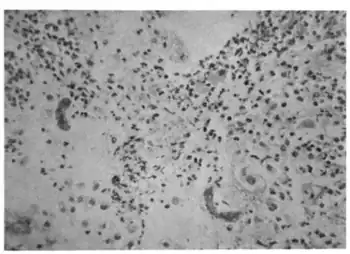

Genes responsible for the maintenance of cell walls in yeast have been shown to be responsible for angiogenesis in vertebrates. Tiabendazole serves to block angiogenesis in both frog embryos and human cells. It has also been shown to serve as a vascular disrupting agent to reduce newly established blood vessels. Tiabendazole has been shown to effectively do this in certain cancer cells.[10]